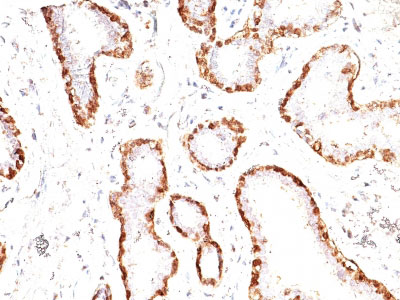

Formalin-fixed, paraffin-embedded human Breast Carcinoma stained with Calponin-1 Monoclonal Antibody (CNN1/832).